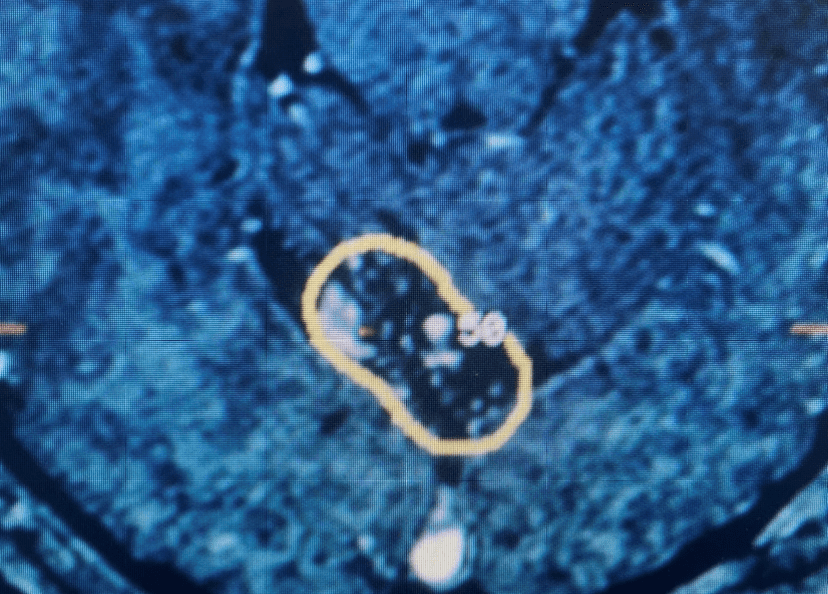

Brain:

Pituitary Tumor with Cushing’s Disease

Author: Michael Brisman M.D., F.A.C.S., Read More!